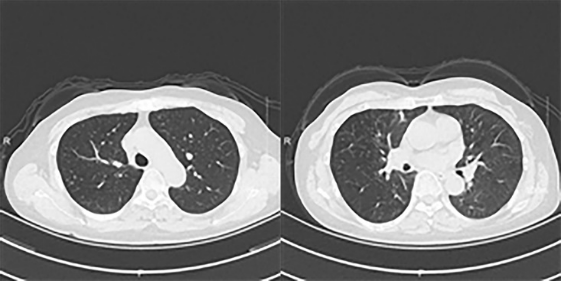

支气管镜检查发现右肺上叶前、尖端可见黏膜充血粗糙,及较多白色坏死物伴堵塞。CT显示双肺支气管壁增厚伴分泌物,右肺上叶多发小结节,两肺少许纤维灶(图1)

1  患者肺部CT

ABPA诊断困难,通常将患者是否患有哮喘作为诊断标准之一。但越来越多报道的ABPA患者既往没有哮喘病史或相关诊断。本文报道这例患者虽未有哮喘、支气管扩张等呼吸系统疾病病史,但有“支气管狭窄”的诊断。而炎症性肺部疾病是易发ABPA的重要因素[6],支气管狭窄也存在炎症浸润的表现,因此极有可能诱发ABPA。此外,我们报道的这例病例CT显示双肺支气管壁增厚伴分泌物,右肺上叶多发小结节,两肺少许纤维灶,同时支气管镜检查发现存在较多白色坏死物堵塞,符合ABPA的影像学诊断。通过实验室检查发现,该患者血清总IgE>2000 IU/ml且烟曲霉特异性IgE为1.50 IU/ml(正常范围0.0~0.34 IU/ml),符合ABPA诊断的必要条件。由于个体存在差异,该患者血嗜酸性粒细胞计数为0.35×109/L,虽未达到诊断标准,但其嗜酸性粒细胞百分比异常升高,因此我们仍可以将该患者判断为嗜酸性粒细胞异常升高的状态。